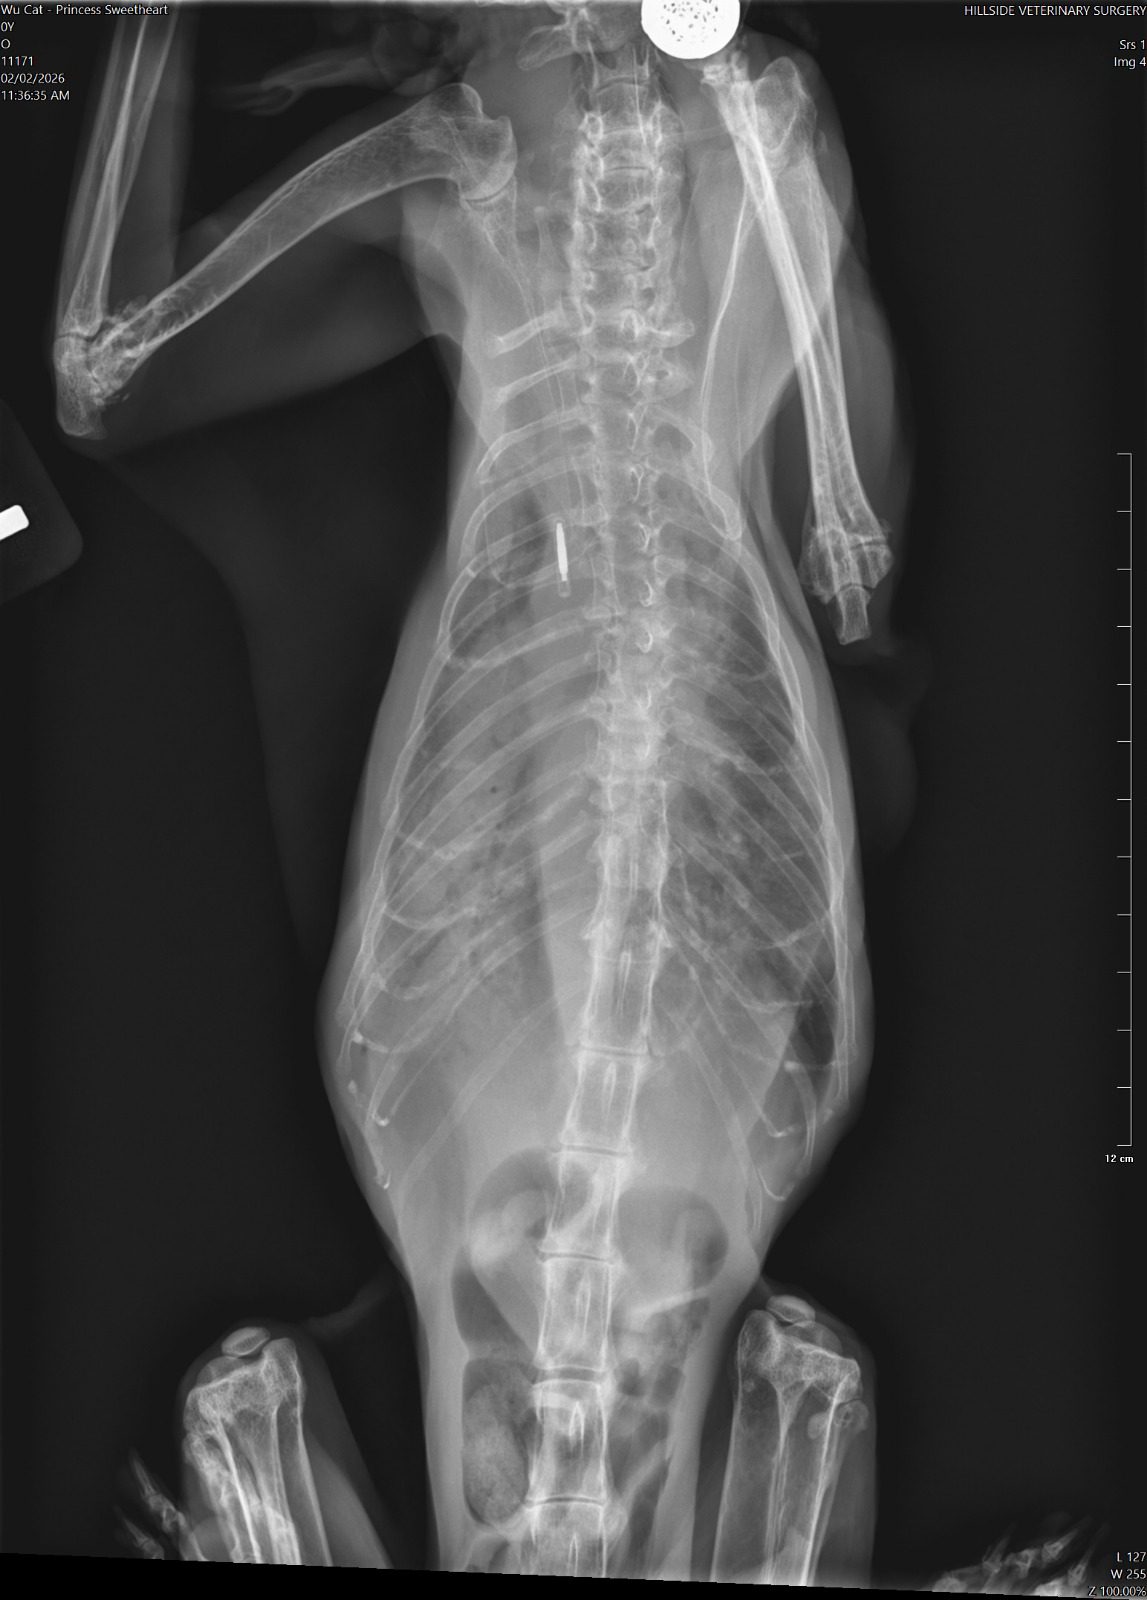

10am+: enter to bring boy for review, princess sianz look. Sleeping even though jo is serving food alr. Weird. I Subcut her as routine but i find her breathing labour. She is really weird. I feel that she might collapse. Jo serve tuna w gravy she is not keen, lucky when I serve tiny pouch she is keen but only take in 5%? Something very wrong she is 喘。 rush her to hillside w ah boy. Alison ard, she bring Ps in first to check, told her Ps is the heart/kidney combo. I taken her RR b4 she go in: 56.

11.15am: Dr Cheryl update: her o2 level low 80% only, she is going to take chest X-ray. most prob is fluid overload her heart le. She wanna retake her bloods, and most prob start frusemide which will stress the kidney but better than if the fluid can’t clear by kidney on time, her heart will fail and she die. That’s what I’m worrying about that why I bring her in cos I know heart scarier. She needs to stay in clinic in o2 for hours, cos to jab frusemide need to monitor in o2. Target 4.00-6.00pm.

Can hear from dr Cheryl tone: it’s serious. Later see the X-ray see how bad. I’ll definitely got to talk to princess let her relax in o2 n wait for me to fetch her when she feel better.

12.50pm; blood drawn, kidney aren’t as bad. Is her heart cannot take it. Lung full of fluid, can’t see her lung so she is a little drowning now, just hide very well. Frusemide given at 12.15pm, only can let frusemide do the job of draining fluid from lung. Can’t poke to draw cos not fluid ard lungs. Dr. Cheryl says Sure (high possibility) die by today. She is not flat yet, definitely panting, knew I’m here again. Sayang her n her head will tilt to me, move a little panting. I didn’t open her cage anything more than 20s. Let her max the use of o2.